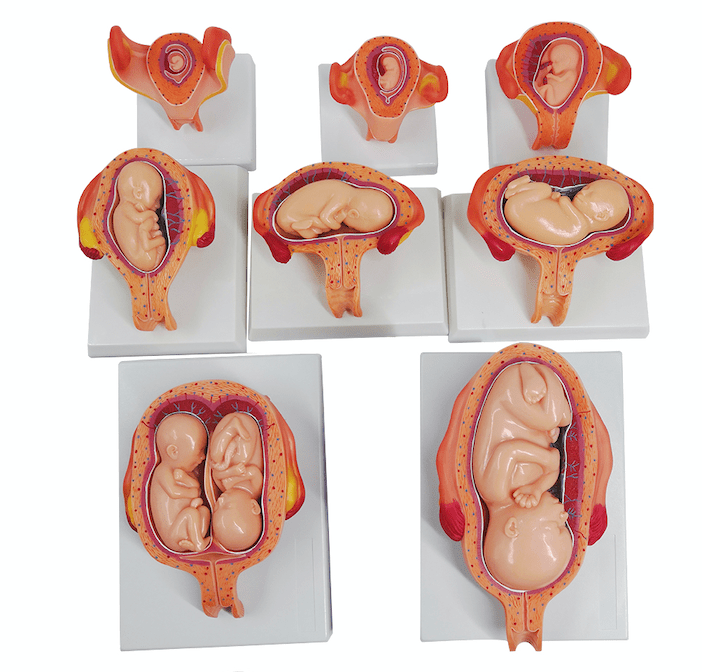

Anatomical models

Selling anatomical models is the mainstay of eAnatomi, although we also spend a lot of resources developing our own anatomical materials such as posters. Anatomical models are used for various purposes and can show both defined tissues, organs and organ systems. Are you looking for a simple model of bone tissue or perhaps an advanced torso model based on MRI technology, you can find it all at eanatomi.com.